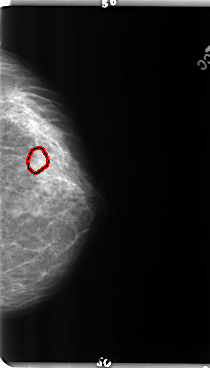

B_3150_1.LEFT_CC

LEFT_CC LINES 4776 PIXELS_PER_LINE 2720 BITS_PER_PIXEL 12 RESOLUTION 50 OVERLAY

FILE: B_3150_1.LEFT_CC.OVERLAY

TOTAL_ABNORMALITIES 1

ABNORMALITY 1

LESION_TYPE CALCIFICATION TYPE PLEOMORPHIC DISTRIBUTION CLUSTERED

ASSESSMENT 4

SUBTLETY 3

PATHOLOGY BENIGN

TOTAL_OUTLINES 1

BOUNDARY